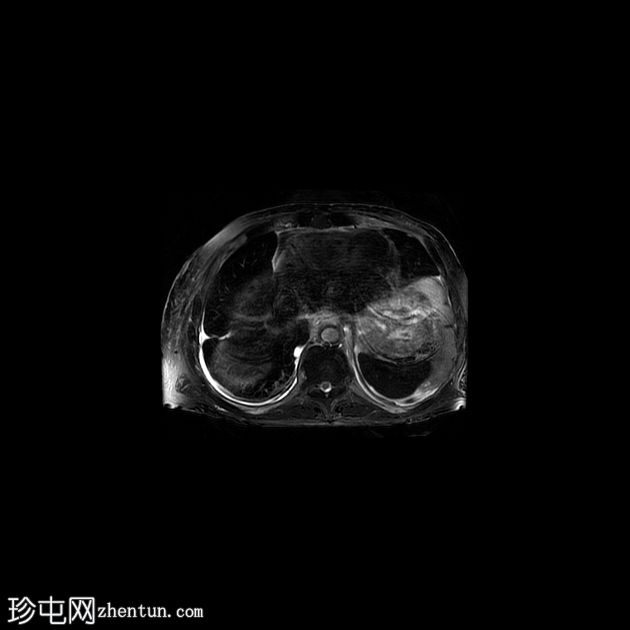

6.jpeg

冠状位 T1

C+脂肪抑制

右髂窝移植肾不规则且受压,肾周可见巨大分叶状肿块,T2呈高信号,并进行性不均匀强化。这是黏液样变性的典型表现。